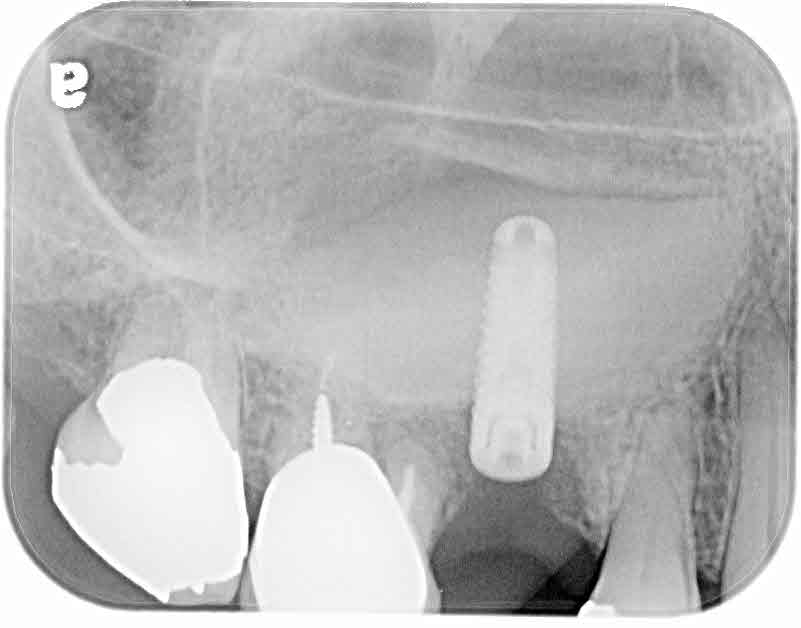

Dr. Roman Itelman performed a minimal invasive sinus lift using the DIVA implant For a 67 year old patient with 4.18 mm bone, using DIVA implant size 3.75/13.

You can see the bone substitute Immediately and 6 month thereafter.